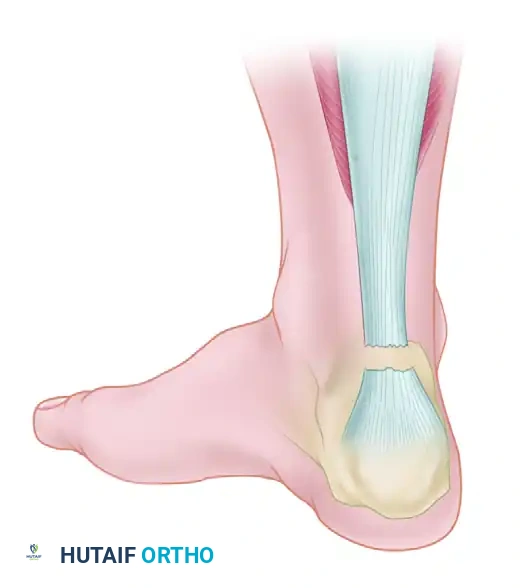

The management of neglected or chronic Achilles tendon ruptures presents a formidable challenge to the orthopedic surgeon. A rupture is generally classified as "neglected" or "chronic" when diagnosis and treatment are delayed for more than 4 to 6 weeks post-injury. During this interval, the proximal gastrocnemius-soleus complex undergoes progressive contracture, fatty infiltration, and atrophy. Simultaneously, the tendon ends retract, and the intervening void fills with disorganized, non-functional fibrotic scar tissue.

Primary end-to-end repair is rarely feasible in these scenarios due to the massive tendon defect (often exceeding 3 to 5 centimeters) and the severe tension that would be placed on the repair, leading to a high risk of wound breakdown and rerupture. Consequently, complex reconstructive techniques are required to bridge the gap, restore the resting length of the musculotendinous unit, and re-establish the biomechanical power of plantar flexion.

Biomechanical Rationale for Flexor Hallucis Longus (FHL) Transfer

When the defect exceeds 5 cm, or when the host tissue is severely degenerated, local tissue advancement is insufficient. Wapner et al. described the use of the FHL tendon as a transfer to reconstruct the Achilles tendon.